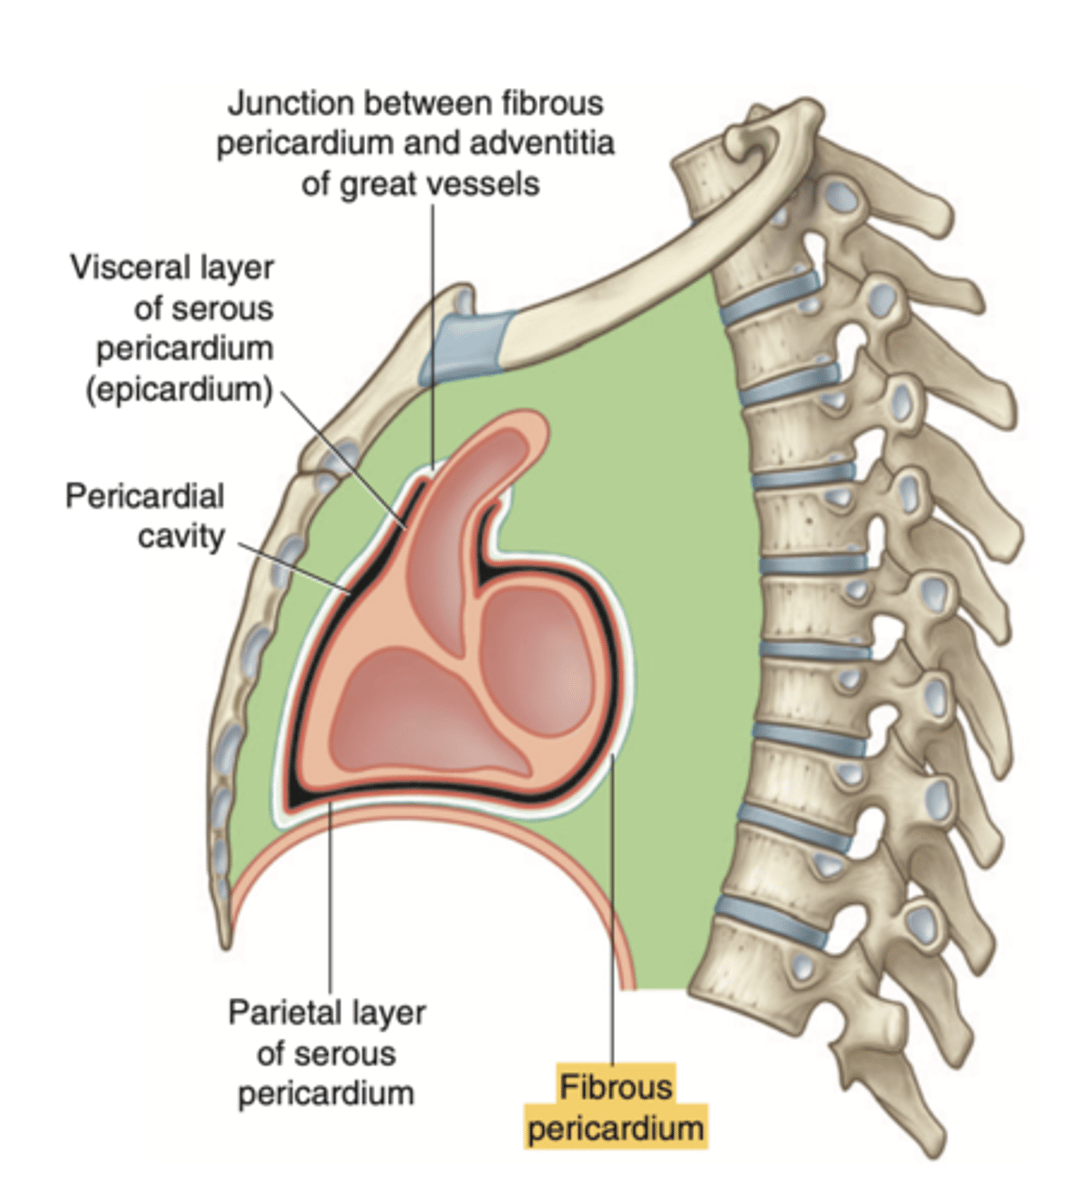

What are the layers of the pericardium?

The pericardium consists of two main layers:

- the fibrous pericardium

- the serous pericardium

How is divided the serous pericardium?

. Visceral layer or Epicardium (innermost). Adheres to the heart

. Parietal layer (outermost)

Between these layers is the pericardial fluid (pericardium cavity )

What is the fibrous pericardium?

the tough, outer layer

protects the heart

maintains its position in the thorax.

defines the boundaries of the medium mediastinum